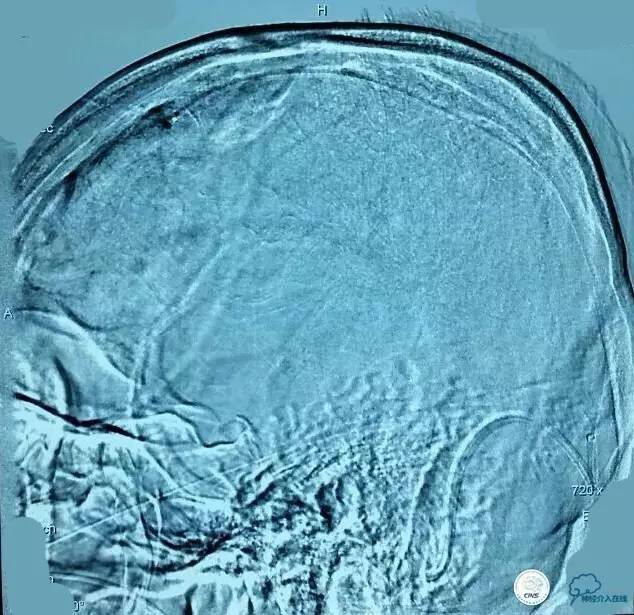

▼术前造影和MRV一致: